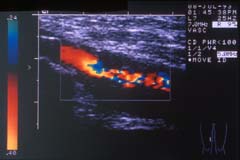

Duplex ultrasound

Ultrasound scanning has become one of the most important investigations used in the assessment of vascular disease. This is because it provides accurate information on the flow of blood in the arteries and veins, but it is painless and risk free. Ultrasound has been used safely for years to assess babies in the womb. The picture on the left shows a modern ultrasound scanner.

Colour flow ultrasound provides accurate information on most arteries. It can assess the flow of blood and whether there is any impairment of flow caused by hardening of the arteries. It is commonly used to assess aortic aneurysms, carotid arteries and the arteries to the legs as in the image (opposite) which demonstrates a narrowing of an artery in the thigh. It is especially useful in the assessment of venous disease as it can identify the sites in the veins leading to reflux (reverse flow).

Ultrasound requires a skilled operator to produce the most accurate information. In some circumstancesthe information obtained from Duplex scanning may be sufficient to make a decision on treatment. This is especially so for carotid surgery but I personally prefer some other supportive imaging before embarking on surgery.